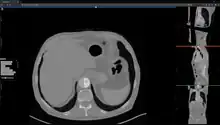

Studierfenster or StudierFenster (SF)[1][2][3] is a free, non-commercial open science client/server-based medical imaging processing online framework. It offers capabilities, like viewing medical data (computed tomography (CT), magnetic resonance imaging (MRI), etc.) in two- and three-dimensional space directly in the standard web browsers, like Google Chrome, Mozilla Firefox, Safari, and Microsoft Edge. Other functionalities are the calculation of medical metrics (dice score[4] and Hausdorff distance[5]), manual slice-by-slice outlining of structures in medical images (segmentation[6][7]), manual placing of (anatomical) landmarks in medical image data, viewing medical data in virtual reality, a facial reconstruction and registration of medical data for augmented reality,[8] one click showcases for COVID-19 and veterinary scans, and a Radiomics module.

Other features of Studierfenster are the automatic cranial implant design with a neural network,[9][10] the inpainting of aortic dissections[11] with a generative adversarial network,[12][13] an automatic aortic landmark detection with deep learning[14] in computed tomography angiography scans, and a GrowCut algorithm implementation for image segmentation.